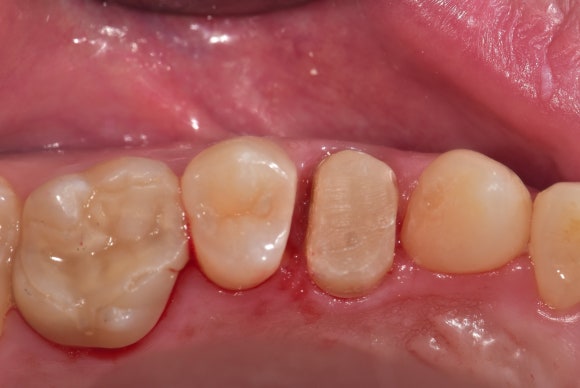

20250414

신경치료 후 단단한 세라믹레진포스트로 기둥을 세워줍니다.

향후 크라운을 씌웠을 때 뿌리와 단단히 잘 연결되어 있게 하기 위해서입니다.

고층건물을 세울 때 철근을 보강하는 것과 같은 원리입니다.